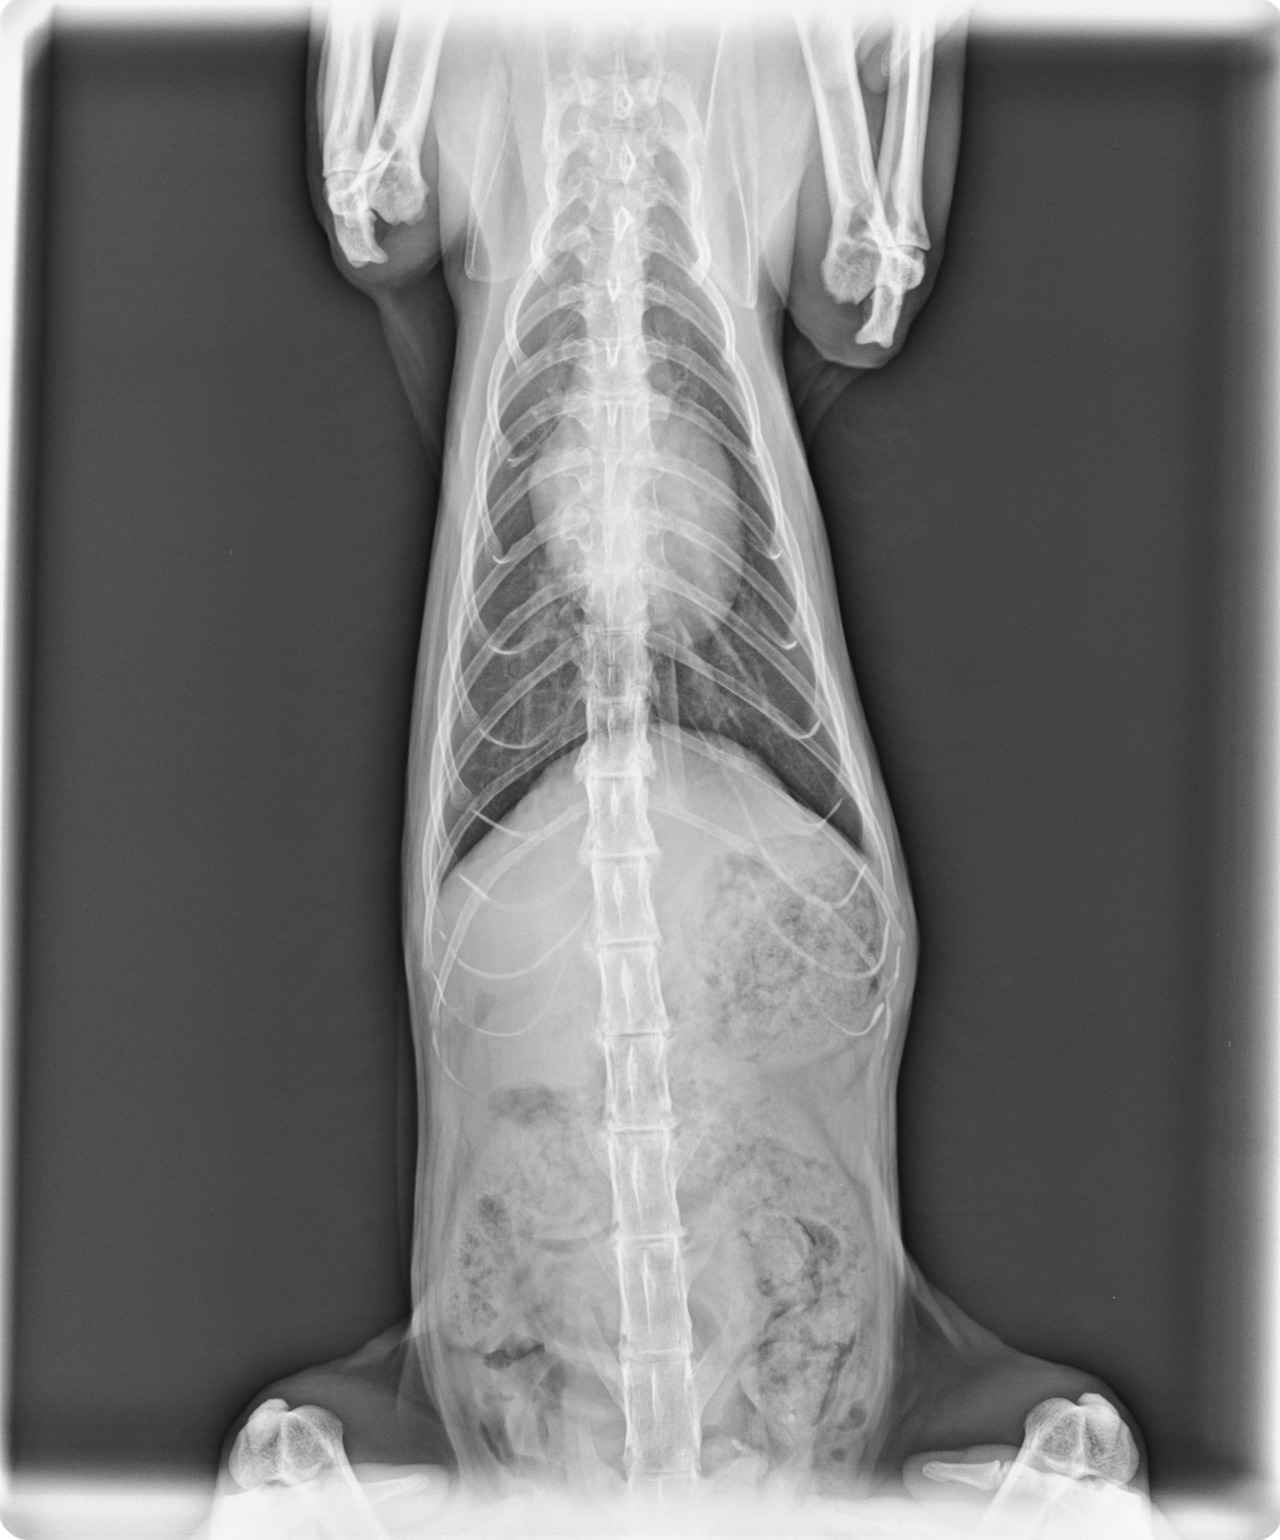

일단 심한 구내염과 피부병은 둘째 치고, 가장 큰 문제는 심장이었다. 이 녀석은 선천적일지도 모르는 심근 비대증을 가지고 있었다. 거기에다 중성화 수술과 미용은 되어있는데, 기본적인 예방접종 항체가 하나도 없었고, 추정 나이는 대략 10살 전후로 보인다고 했다.

아마도 이 녀석의 전 주인은 중성화 수술은 했지만 예방접종은 하지 않았고(했다 하더라도 항체가 없어졌거나), 심장병이 있는 나이 든 이 녀석을 근처에 민가 하나 없는 외딴 산속에 버려두고 간 것이라고 추측할 수밖에 없었다. 담담히 설명해주시는 수의사님 앞에서 주책없는 눈물만 줄줄 흘렀다. 이 녀석의 처지가 너무 불쌍해서.. 처음 나를 찾아왔을 때의 그 고단했던 모습이 떠올라서...

이어서 들었던 수의사 선생님의 말씀은 나를 더 슬프게 했다. 지금 이 녀석은 당장 내일 무지개 다리를 건너도 이상하지 않은 상태라고.

일단 심근 비대증 때문에라도 평생 약을 먹고살아야 되는데, 그 날부터 이 순둥한 녀석과의 약 먹이기 씨름이 시작되었다. 먹지 않으려는 자와 먹이려는 자. 그 싸움의 끝은 결국..